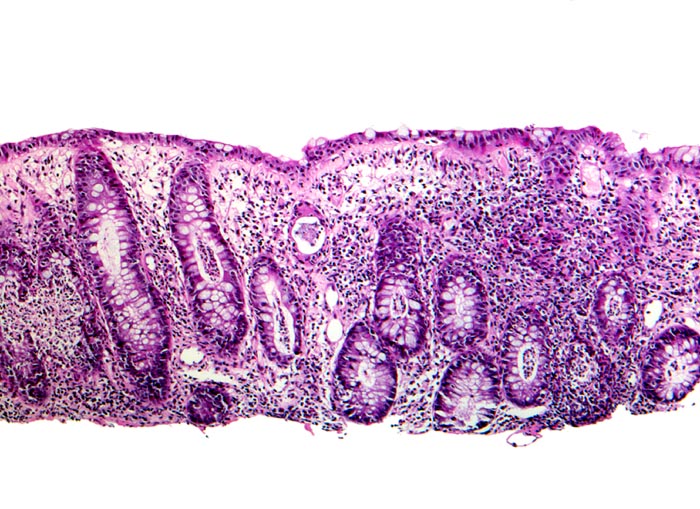

Infektiöse Kolitis

Entzündung infektiös

Kolon

Akute Kolitis mit zahlreichen

Kryptenabszessen und eitriger Kryptitis. Die Kryptenarchitektur ist weitgehend erhalten und die Anzahl Becherzellen kaum vermindert.

Histologie

50